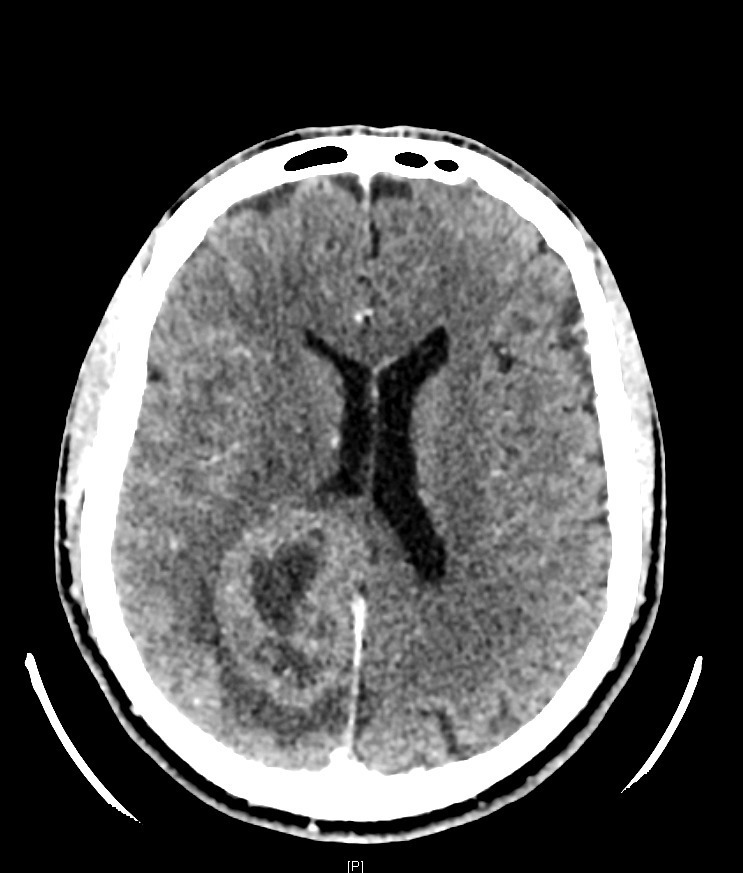

M. V., 41 ans, droitier, est adressé aux urgences où vous exercez, pour un épisode de mouvements cloniques hémicorporels gauches durant près de 10 minutes, sans perte de connaissance, avec un teint bleuté.

Son épouse ne rapporte pas d’antécédent particulier, il ne présente pas de troubles cognitifs. Elle signale tout de même que cela fait plusieurs fois qu’elle touche le bras gauche de son mari sans qu’il ne s’en aperçoive. De plus, il a récemment endommagé le rétroviseur côté conducteur de leur véhicule lors d’une manœuvre de stationnement. Il ne prend pas de traitement. Il ne fume pas et ne boit qu’occasionnellement. Il est sportif, en bon état général par ailleurs. Il se plaint parfois de céphalées avec sensation d’étaux, prédominantes à droite, qui résistaient aux antalgiques simples (paracétamol) depuis plus de 3 semaines.

Cliniquement, vous constatez une hémiparésie brachio-faciale gauche, apparue juste après l’épisode de mouvements anormaux et qui semble être en train de régresser selon les pompiers.